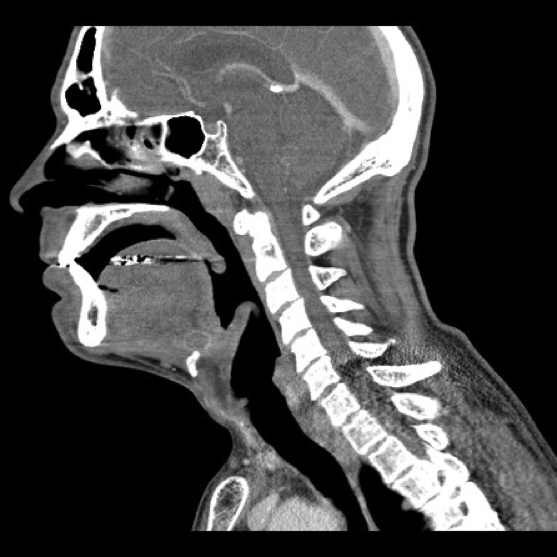

- Thyroglossal Duct Cyst with ring enhancement on CT:

- Figure 36 and 37. Thyroglossal Duct Cyst on CT